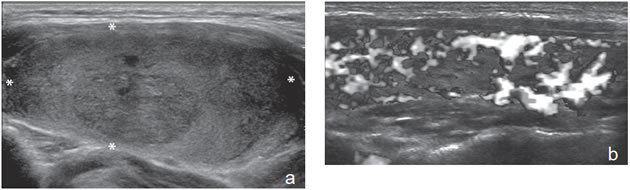

Figura 31. Área hipoecogénica en el lóbulo tiroideo aumentado de

volumen (asteriscos) que corresponde a un foco de tiroiditis de De

Quervain, que simula un tumor maligno.